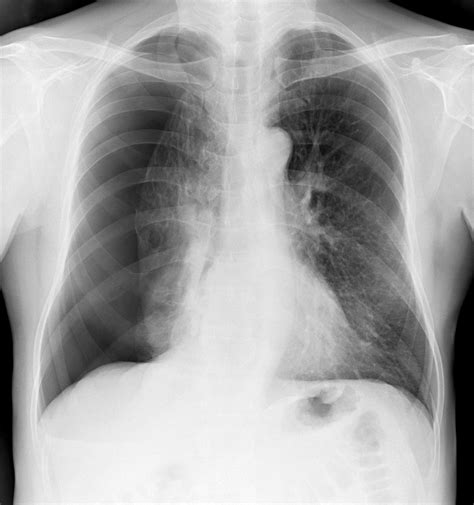

Diagnosing Atelectasis Lung Cancer involves a combination of medical history, physical examination, and diagnostic tests. The diagnostic process typically includes:

• Chest X-ray: An initial imaging test to detect any abnormalities in the lungs.